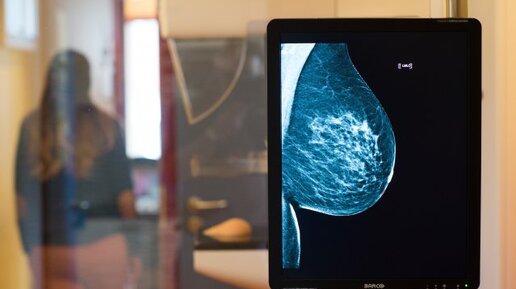

Обследование молочных желез начинают с простых методов, которые максимально безвредны для организма. Для женщин после 40 лет это маммография – рентгенологический способ диагностики молочных желез, который помогает найти доброкачественные и злокачественные образования в груди. Достоинства маммографии В молодости маммография используется редко, врачи рекомендуют делать УЗИ, что связано с особенностями строения тканей. После 40 в груди увеличивается содержание жировой ткани, поэтому рентгеновские лечи проходят лучше и дают четкое изображение структуры железы...

Маммография или УЗИ? Что выбрать? Основная разница между УЗИ и маммографией — как не пропустить рак молочной железы